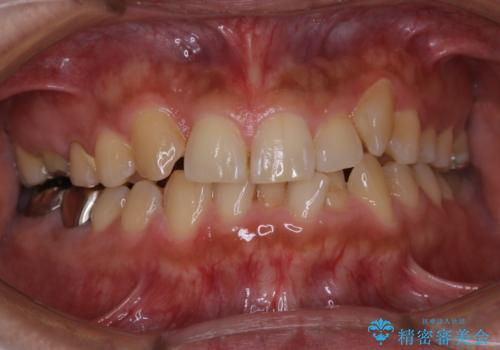

前歯メインにステインの付着が見られ、コース内容を相談した結果PMTC(保険外治療)の30分コースを行いました。